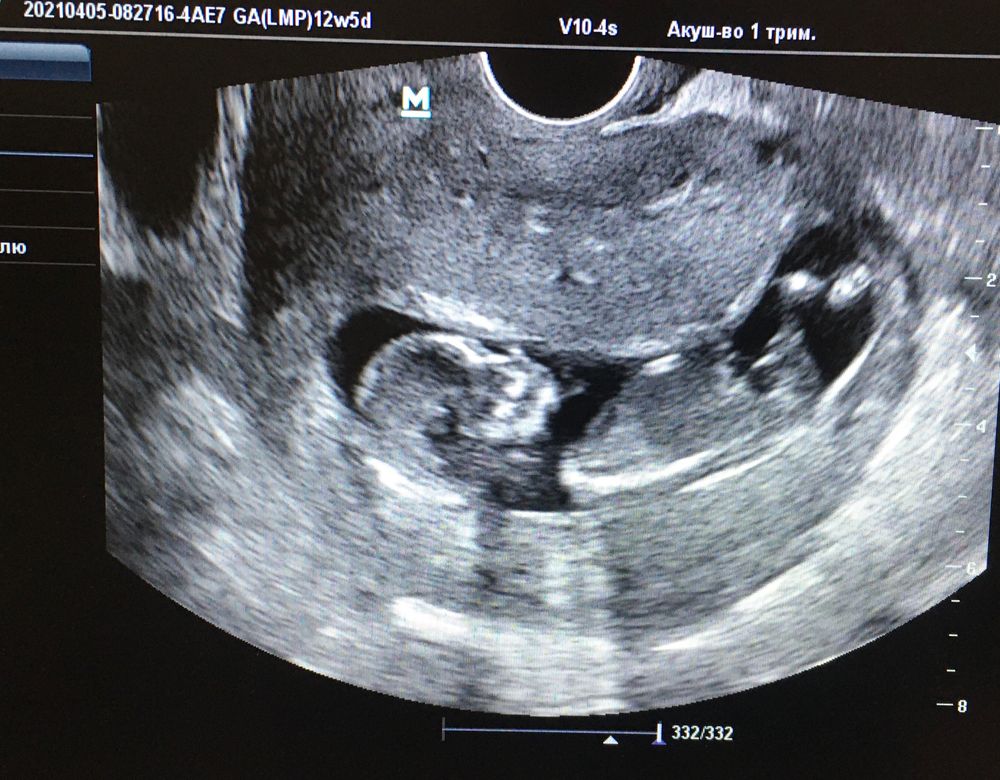

Пошла на приём к гинекологу, она послушала, посмотрела меня и... выписала направление на узи с замершей беременностью. Приём был в пт, а узи во вт. Со мной пойти не кому было, отправили отца моего. Надо ли говорить, что я все эти дни ревела, а путь на узи проходил через ж/д.

Рамзи. Сделала поздновато, но предположили М

С первого скрининга